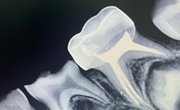

Our state-of-the-art manufacturing process for preformed dental crowns ensures highly accurate, custom-fit restorations, enhancing both clinical outcomes and patient satisfaction.

Our crowns are crafted with unmatched accuracy using the latest digital technology, ensuring a perfect fit and superior functionality for every patient.

We use only the finest materials ensuring that every crown offers exceptional strength, wear resistance, and a natural appearance.